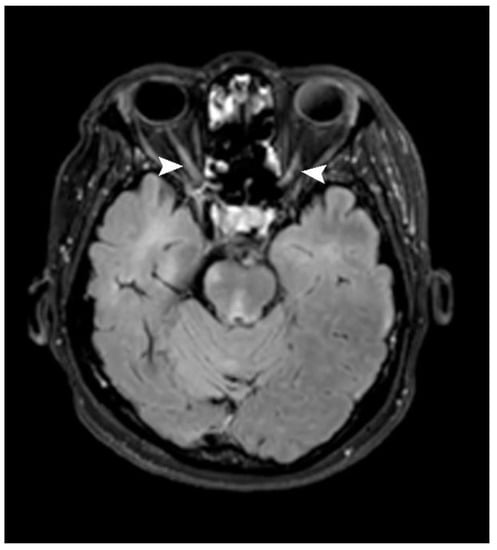

Optic nerve lesions were identified in seven patients (21.9%). A unilateral lesion and bilateral lesions were found in three and four patients (42.9 and 57.1%), respectively. A long-segment lesion (longer than 50% of the optic nerve length) was identified in only one patient, while the remainder showed short-segment lesions (six patients, 85.7%). Of these, four showed posterior-half lesions (66.7%; Figure 6, Table 2).

Figure 6.

Axial post-contrast FLAIR image shows patchy enhancement at posterior halves of bilateral optic nerves (arrowhead) in keeping with bilateral optic neuritis.

This study showed some similarities with previous studies conducted in Thailand [13]. Firstly, similar age groups and a high female-to-male ratio were noted in both studies. Regarding the MRIs, we also found that the periventricular region was the most common lesion location (78.1% in our study and 52.8% in Jitpratoom’s study). Jitpratoom et al. [13] also found that the juxtacortical region was the second most common location. Regarding the spinal MRI, Jitpratoom found that the mean length of the spinal cord lesions was 1.29 vertebral segments, whereas our study showed a mean spinal cord lesion length of about 2.2 vertebral segments [13]. Another study performed in Thailand [12] showed negative spinal MRIs in 41.9% of all the patients, with the remaining patients with positive MRIs showing cervical and thoracic spinal cord lesion in 48.4 and 29.0%, respectively. Our study showed a much higher proportion of positive MRIs (23 out of 26 patients with available spinal MRIs, 88.5%). The performance of spinal MRIs on patients with suspected spinal lesions only in our institute may have contributed to the high positive rate. Our study also identified that most of the patients had both cervical and thoracic spinal cord lesions (11 patients, 47.8%), with a cervical lesion alone or a thoracic lesion alone in seven and four patients, respectively. Tritrakarn et al. also collected data about optic nerves, showing optic nerve lesions in four of thirty patients, of whom three patients had lesions in the anterior half of the optic nerve [12]. Our study showed optic nerve lesions in seven of thirty-two patients. Of these, six short-segmental lesions were identified, of which four were located in the posterior half of the optic nerve.